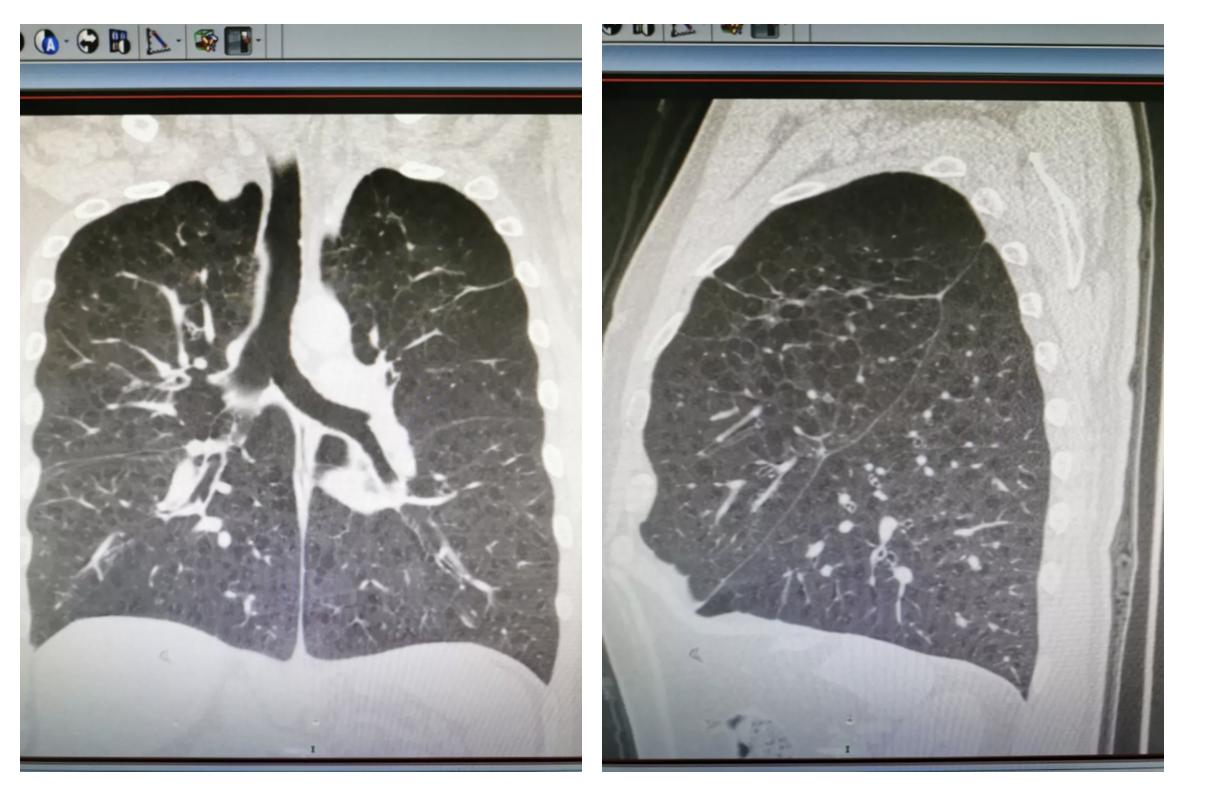

右图是一位慢阻肺患者的胸片,跟正常的肺部相比,这种肺被称为 「桶状胸」 。

图为该患者胸部X线片显示为桶状胸:胸廓的前后径增加

「所谓桶状胸是指胸廓前后径增加,有时与左右径几乎相等,呈圆桶状,又称“气肿胸”。」金哲医生介绍,正常人的胸廓前后径和横径比值是1:1.5,桶状胸时前后径和横径相比是1:1,也就是变圆了,不是椭圆了,所以称之为桶状胸。